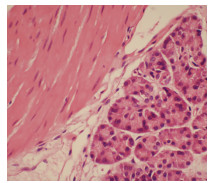

Lymphoepithelioma-like hepatocellular carcinoma: A case report

Xiaotong QIU, Zhengqi WU, Xuxiang XIA, Guoyue LYU

2022, 38(3): 634-635. DOI: 10.3969/j.issn.1001-5256.2022.03.027

Abstract(762) HTML (934) PDF (2924KB)(68)

Abstract: